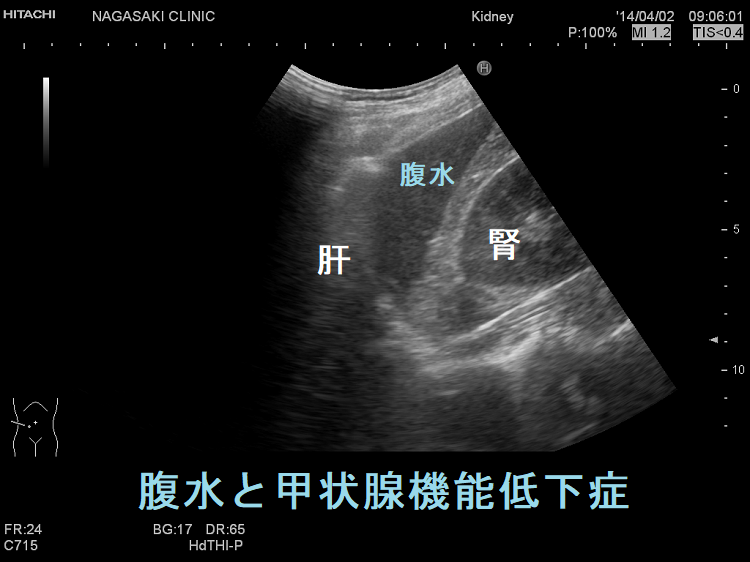

甲状腺機能低下症の4%未満に腹水(蛋白濃度が高い粘液水腫性腹水)。粘液水腫性腹水自体が腹膜を刺激し、卵巣癌の腫瘍マーカーCA125 の産生を増加させる。甲状腺ホルモン(チラーヂンS)補充療法により腹水は消失し、約1カ月遅れてCA125も正常値に。特に甲状腺ホルモン値(FT4,FT3)が低いと粘液水腫性腹水(腹水穿刺・利尿剤に反応悪く改善に時間を要す)・胸水(利尿剤で速やかに消失)・心嚢液(肺水腫、呼吸困難、右心不全、陰嚢・両下腿浮腫)貯留、腸管浮腫[甲状腺ホルモン剤(チラーヂンS)吸収障害]が出現。甲状腺乳頭癌、甲状腺未分化癌の腹膜播種がある。

粘液水腫性腹水自体が腹膜を刺激し、卵巣癌の腫瘍マーカーであるCA125 の産生を増加させると考えられます。大量の腹水があって、血清CA125も異常高値なら卵巣癌の腹膜びまん性転移(癌性腹膜炎)を疑いますが、実は卵巣癌ではなく甲状腺機能低下症が原因なのです。報告では血清CA125が822 U/mL(<35 U/mL)まで上昇したそうです。

甲状腺ホルモン(チラーヂンS)補充療法により腹水は消失して、CA125も正常値になります(甲状腺ホルモン正常化後、約1カ月遅れて)。

甲状腺機能低下症で、特に血中の甲状腺ホルモン値(FT4,FT3)が低いと、粘液水腫による腹水・胸水・心嚢液が貯留し易くなります。